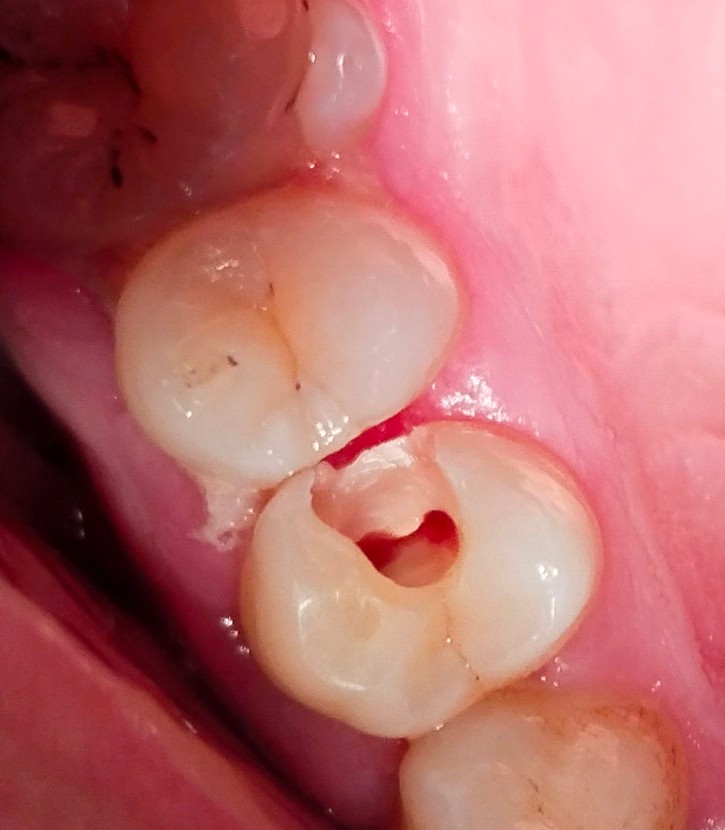

Utilizing rotary endodontics, we performed the RCT on Rahim’s upper right first premolar, known for often having two canals. In Rahim’s case, we confirmed the presence of two canals—the buccal canal measuring 21mm and the palatal canal measuring 22mm. Despite the complexity, the advanced techniques ensured precise treatment and Rahim’s comfort.

It’s crucial to note that the success of Root canal treatment depends significantly on proper technique. Using an X-ray and sensor from Eighteeth for working length confirmation of root canals, we ensured a precise understanding of the working length. In many failed RCT cases, under-obturation is observed, highlighting the importance of thoroughly cleaning the canal to the apex and then well-obturating it for a successful outcome.